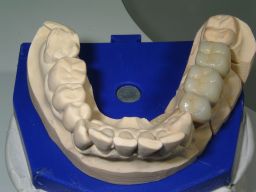

Zähne mit Amalgamfüllungen für Kronen vorbereitet

Die 3 Kronen auf dem Gipsmodell

Die Patientin wünschte eine dauerhafte, weiße Versorgung. Übrigens: Die Weltgesundheitsorganisation (WHO) hält wie die internationale Vereinigung der Zahnärzte (FDI) Amalgam für sicher. Auch neueste Arbeiten (1, 2, 3) haben an der Einschätzung nichts geändert.